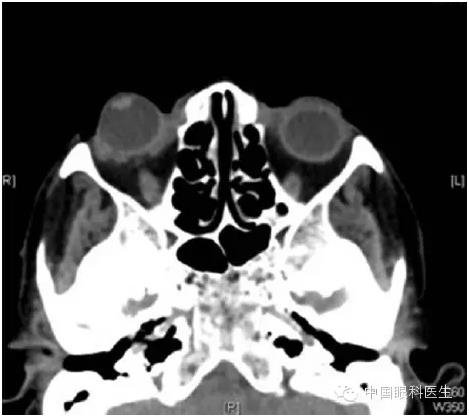

一名 65 岁女性因右眼剧烈疼痛就诊于我院急诊,自述 3 小时前有右眼门把手外伤史。查体发现右眼视力为手动,上下眼睑均位于脱位的眼球后,眼压为 54mmHg,角膜水肿,前房较深,视网膜窥不甚清(图 1)。左眼检查无明显异常。急诊首诊医生诊断为球后出血,急予以头颅及眼眶 CT 扫描,CT 则仅发现眼球脱位、眼睑肿胀,并无颅内、眶内出血抑或眶壁骨折的征象(图 2),B 超检查并未发现视神经撕脱的证据。

▲ 图 2 眼眶 CT 无眶内出血及眼眶骨折